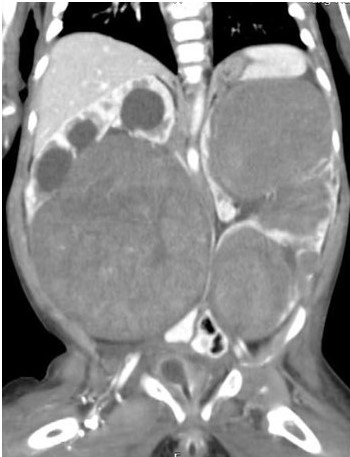

An 8 month old girl with hypoplastic corpus callosum, epilepsy and bilateral hydronephrosis presented with abdominal distension due to an abdominal mass occupying almost all quadrants. Ultrasonography could not define the organ of origin and CECT (contrast enhanced CT) abdomen showed a right-side renal mass (11 × 10.5 cm) occupying the mid and lower pole with hydronephrosis, and three well defined masses in the upper, mid, and lower pole of the left kidney, measuring 7 × 5cm, 4.3 × 4cm and 7 × 6.7cm respectively (Figure 1). A bilateral trucut biopsy revealed nephroblastoma on either side. Metastatic work up was negative, and she underwent neoadjuvant chemotherapy with Vincristine and Actinomycin. Reassessment with CT abdomen after 6 weeks showed good response in the left kidney, however only slight reduction in size of the right-side mass. The child underwent an initial, Nephron-Sparing Surgery (NSS) on the right side (Figures 2a,2b) with negative margins and negative sampled lymph nodes (LN). Hence post-operative chemotherapy was administered as local Stage II. After a month, DMSA scintigraphy (Dimercaptosuccinic Acid) showed good function in the residual right kidney and a left radical nephrectomy was done (nodes negative). Histopathology on both sides revealed a favourable type of WT. The child is now 5 year old, and at latest follow has no recurrence and excellent renal function.

Figure 1. CECT showing bilateral Wilms tumor